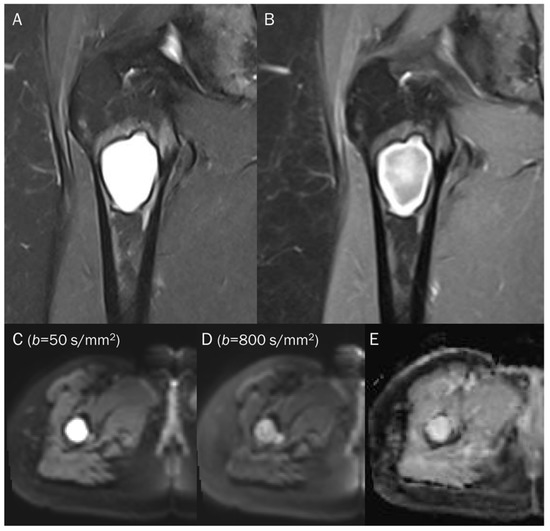

7.3. Benign Bone and Soft Tissue Tumors

| Benign tumors | ||

| Non-ossifying fibroma | T2 black-out | Collagen fibers |

| Giant-cell tumor | T2 black-out | Hemosiderin |

| Gouty tophi | T2 black-out | Monosodium urate crystal |